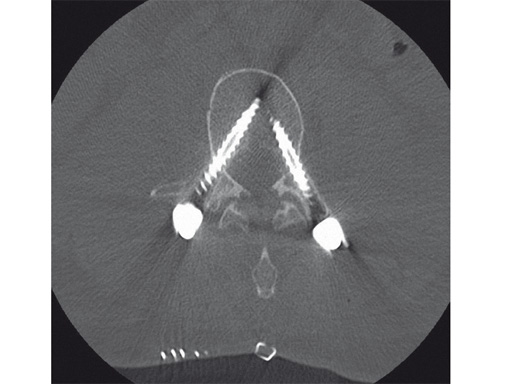

Intraoperative CT scans can be obtained using image-intensification- based isocentric C-arms, portable cone beam CT (O-arm, Medtronic) or true intraoperative CT scanners (iCT). Isocentric C-arms and portable scanners offer the advantage that they can also be used as regular C-arms, however their imaging quality may be inferior to stationary CT scans (Fig 3).

Fig 3ac a Intraoperative CT scans from an image-intensification-based isocentric C-arm. The software allows simulation of various diameter and length screws. bc Comparison of intraoperative simulation and postoperative CT scan shows the high accuracy of CAS.